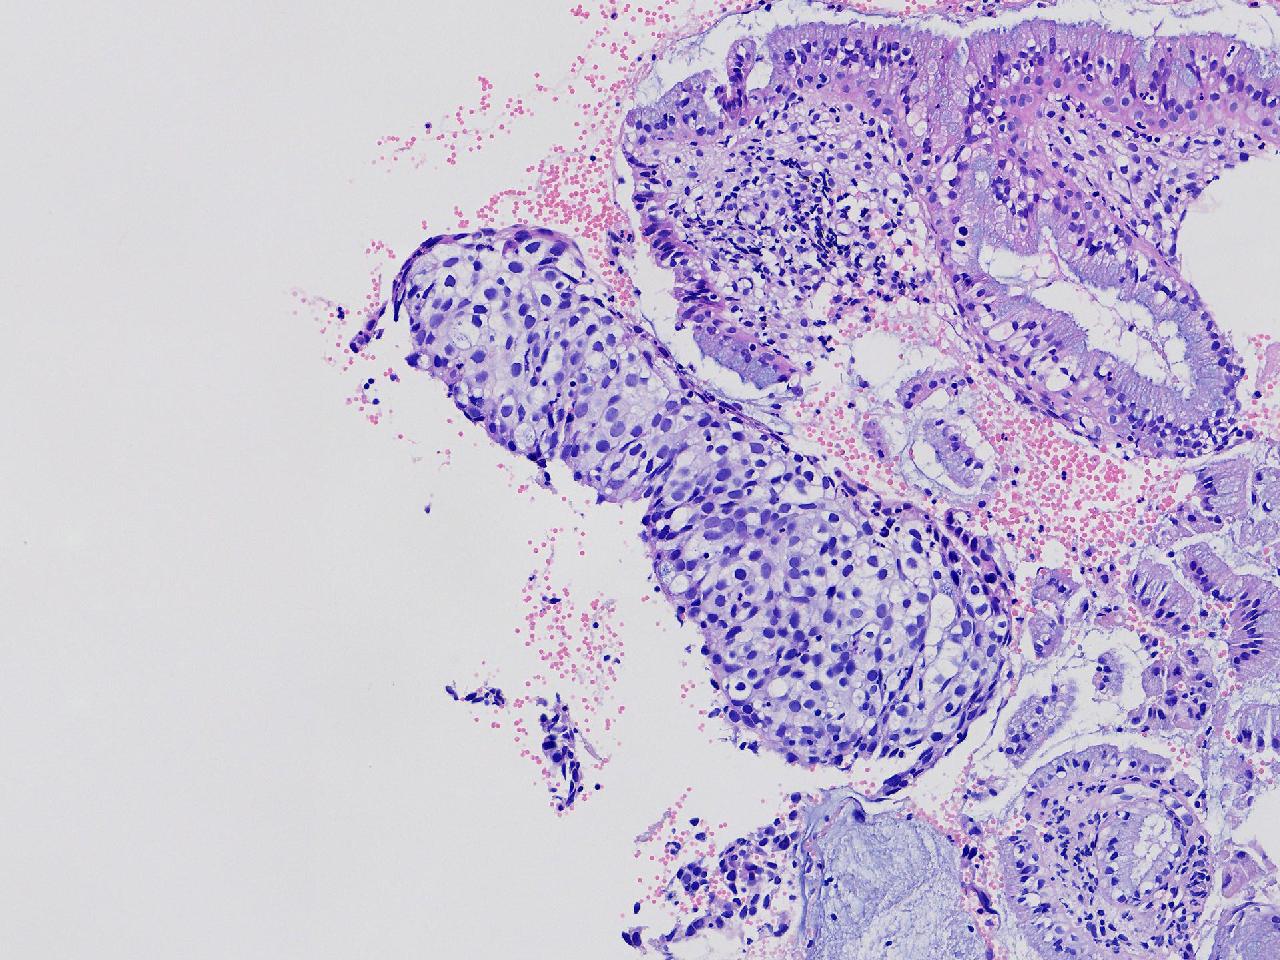

宫颈管活检,这块鳞皮CIN2级?

性别

女

年龄

47岁

临床诊断

另外送检分泌期样子宫内膜和内膜息肉,没有上传图片。

一般病史

阴道出血10余天,伴血块,带环10余年。

标本名称

宫颈管活检

大体所见

灰粉色不整形软组织多块,0.8x0.5x0.3厘米,全部取材。

高级别CIN2

标一下P16和Ki67看看。